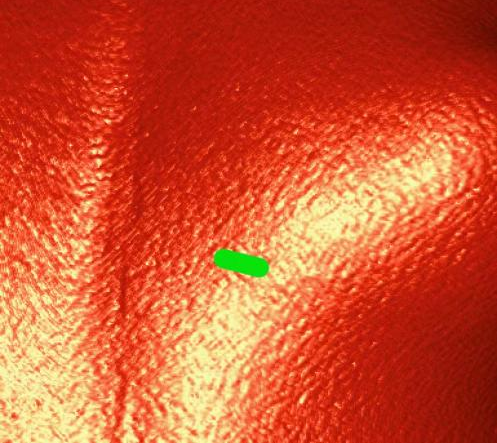

模拟肋间切口位置

在安琪教授的主持下,多学科讨论后认为该患者上述解剖特点不适合目前经股静脉入路植入的介入肺动脉瓣,可考虑使用佰仁医疗Salus介入肺动脉瓣经心尖入路实施肺动脉瓣植入。在心脏大血管外科安琪教授主持下,心脏内科冯沅教授带领赵振刚副教授及李翔医师与心脏大血管外科罗书画副主任医师及李东旭主治医师合作完成了手术。术中手术团队经股静脉完成心导管检查及造影后,通过肋间小切口暴露右室心尖并预置荷包缝线,穿刺右室心尖建立经心尖入路,而后分别经股静脉和心尖进行左、右肺动脉球囊对吻扩张,最后经心尖完成肺动脉瓣植入。术后TEE提示肺动脉瓣植入位置理想、固定良好,无瓣周漏或中央反流,左、右肺动脉显影正常。肋间切口长度仅2.5cm,总体手术效果满意。